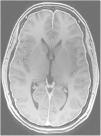

Pruebas de neuroimagenLa resonancia magnética (RM) craneal es la prueba fundamental en el diagnóstico, sobre todo para descartar otras causas de hipertensión intracraneal y debe incluir siempre una venografía, para descartar, principalmente, una trombosis de senos. Los hallazgos en RM pueden ser muy sugestivos, pero no son patognomónicos ni definitorios de HII. Los más típicos son la silla turca vacía parcial o total, en la órbita se suele observar un aplanamiento posterior del globo ocular o incluso un abombamiento de la papila hacia el vítreo, tortuosidad de los nervios ópticos con aumento del grosor de la vaina, pero todos ellos no son específicos, pues pueden encontrarse en individuos sanos, aun así, cuando se encuentran de forma combinada aumentan la sensibilidad24,25.

TC craneal: suele ser normal, aunque se han descrito senos venosos ingurgitados, ventrículos pequeños, colecciones de fluidos subdurales (fig. 4), obliteración de la cisterna prepontina e imágenes de pseudohemorragia subaracnoidea (hiperdensidad del tentorio y en la cisura de Silvio)49.

RM cerebral con gadolinio (Gd+) iv: es la exploración de neuroimagen de elección para confirmar la sospecha clínica de HIE, siendo diagnóstica en un 80%49. Se han comunicado sus resultados en más de 2.000 pacientes con HIE y los signos informados aparecen en la tabla 1048,49. La captación paquimeníngea de Gd+, difusa y homogénea, es el signo radiológico más frecuente (fig. 2). No obstante, la valoración de estos signos radiológicos requiere entrenamiento para evitar arbitrariedad. Por ello, se han desarrollados escalas como la de Bern (tabla 11)59,60. Los hallazgos en la RM dependen del tiempo de evolución de la enfermedad61.

Tabla 10.Signos radiológicos de HIE en RM craneal

■ Captación paquimeníngea difusa de Gd+ (73-80%) que en la mayoría de los casos se puede apreciar también en secuencia FLAIR sin Gd+. (fig. 2) ■ Colecciones de fluidos extra-axiales (35-50%), siendo el 60% higromas y el 40% hematomas (fig. 4) ■ Descenso cerebral desproporcionado al tamaño de las colecciones de fluidos (43%). Pueden aparecer los siguientes signos: ■ Colapso ventricular ■ Angulación del quiasma óptico ■ Aplanamiento de la protuberancia contra el clivus con obliteración de la cisterna pontina, ■ Descenso del cuerpo calloso ■ Descenso amigdalar ■ Ingurgitación venosa (57%) ■ Aumento del tamaño hipofisario (38%) ■ Pneumoencéfalo intraventricular (fig. 5) en casos de HIE yatrogénico ■ Disminución del diámetro y grosor del nervio óptico en secuencia coronal T2, también detectable con ecografía transorbitaria Tabla 11.Escala de Bern. Signos de HIE en RM craneal